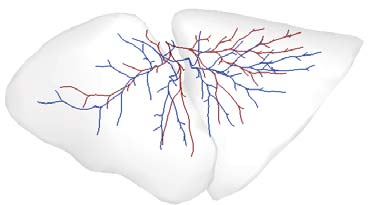

Recent advances in imaging techniques have enabled us to visualize lung tumors or nodules in early-stage cancer. However, the positions of nodules can change because of intraoperative lung deflation, and the modeling of pneumothorax-associated deformation remains a challenging issue for intraoperative tumor localization. In this study, we introduce spatial and geometric analysis methods for inflated/deflated lungs and discuss heterogeneity in pneumothorax-associated deformation. Contrast-enhanced CT images simulating intraoperative conditions were acquired from live Beagle dogs. Deformable mesh registration techniques were designed to map the surface and subsurface tissues of lung lobes. The developed framework addressed local mismatches of bronchial tree structures and achieved stable registration with a Hausdorff distance of less than 1 mm and a target registration error of less than 5 mm. Our results show that the strain of lung parenchyma was 35% higher than that of bronchi, and that subsurface deformation in the deflated lung is heterogeneous.